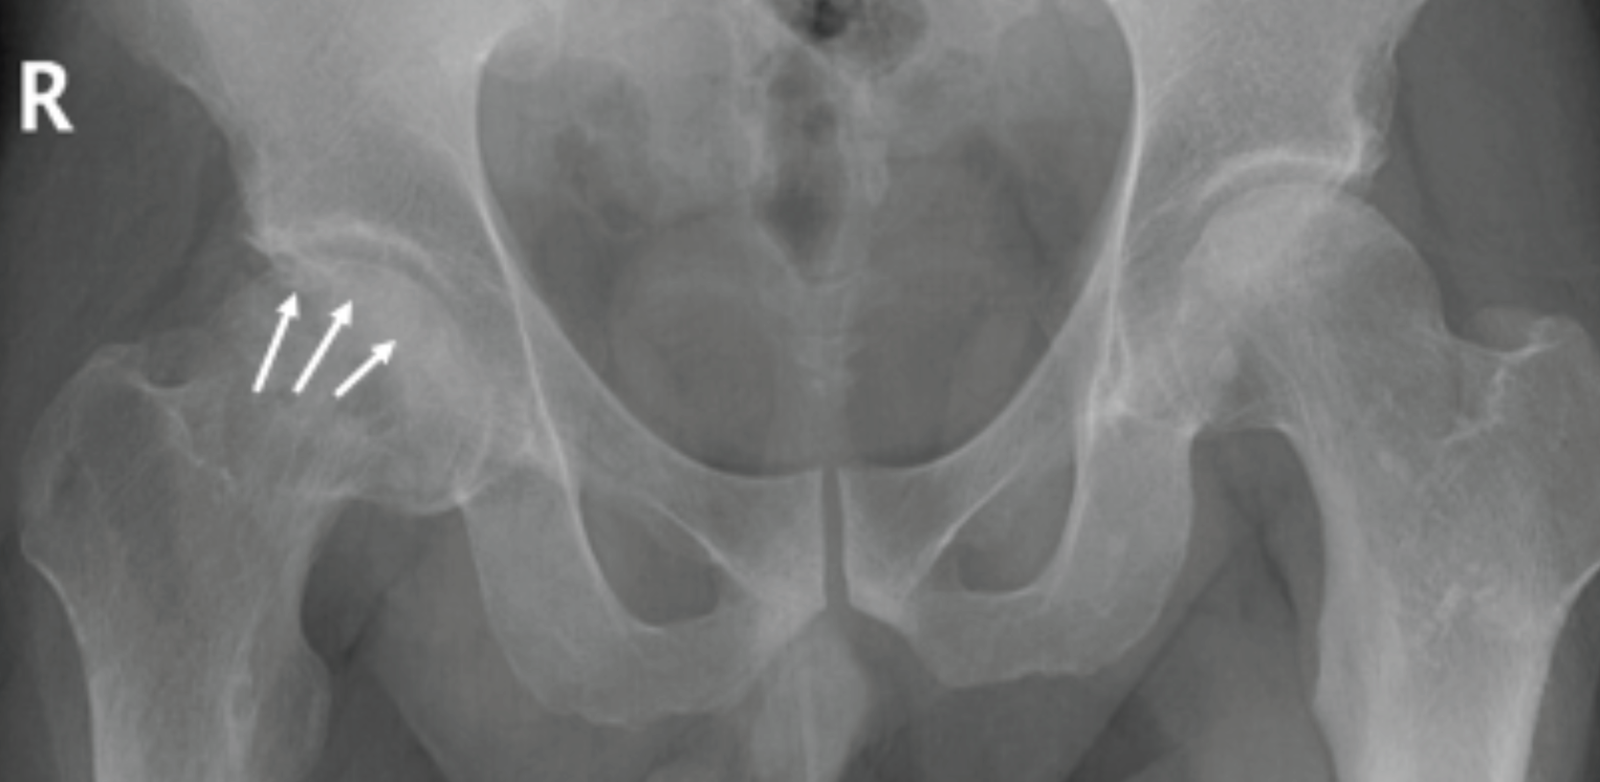

Röntgen: Avasküler nekrozun ilerleyen aşamalarında meydana gelen kemik değişikliklerini ortaya çıkarabilirler. Durumun erken aşamalarında, röntgenler genellikle herhangi bir bulgu vermez.

İleri evre kalça osteonekrozunda femur başının şekli bozulmuş.